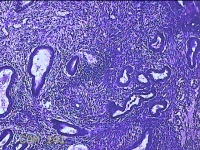

性别

女

年龄

46岁

临床诊断

异常子宫出血

一般病史

经净后阴道流血2天。

标本名称

宫腔赘生物

大体所见

灰白粉红色不规则肿物1.3x1.2x0.3cm一堆,表面光滑。

图2